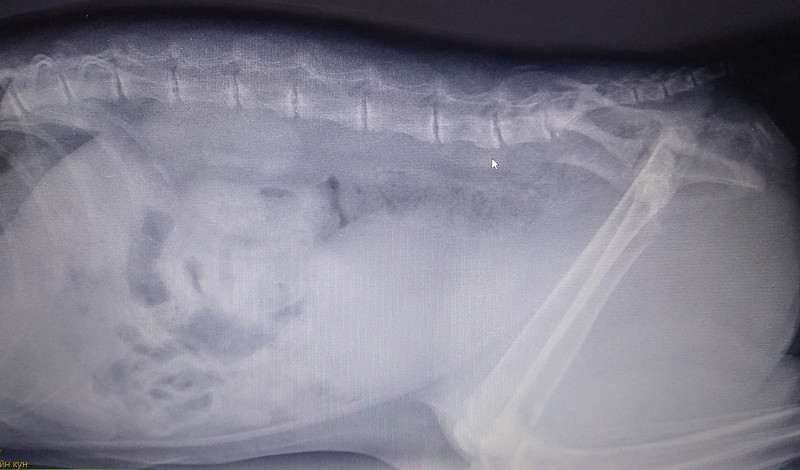

13.10.18 был сделан рентген. Там врач увидела перелом. Сказала нужна операция. И выписала травматин, анальгивет и корм мобилити. Уколы были проставлены один раз там же в клинике.

Снимки также были отправлены по вот сап и показаны 2-ум другим врачам один ничего не увидел. другой увидел смещение.

У котика кальций к нулю движется. Кости на снимке практически сливаются с мягкими тканями и вряд ли это только из-за качества снимка.